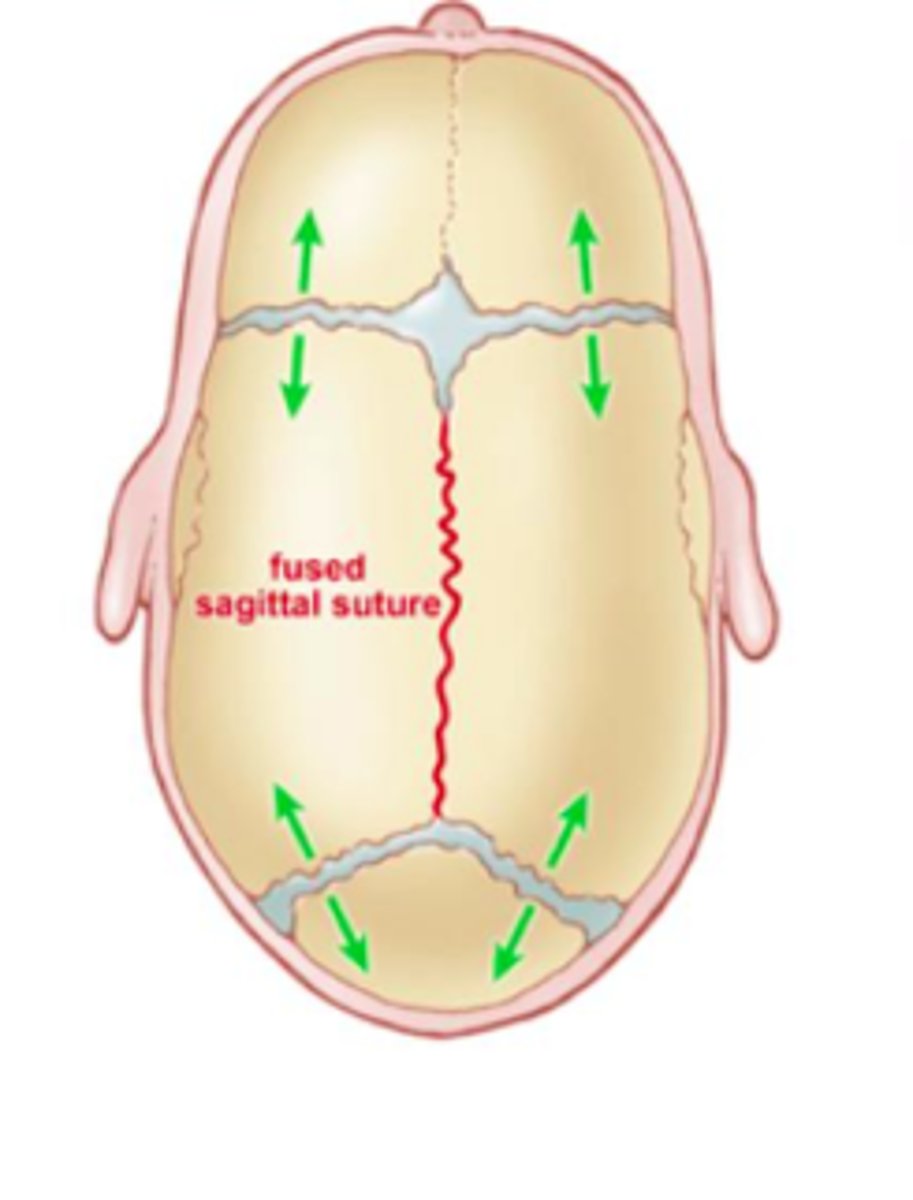

Craniosynostosis

Premature fusing of sutures